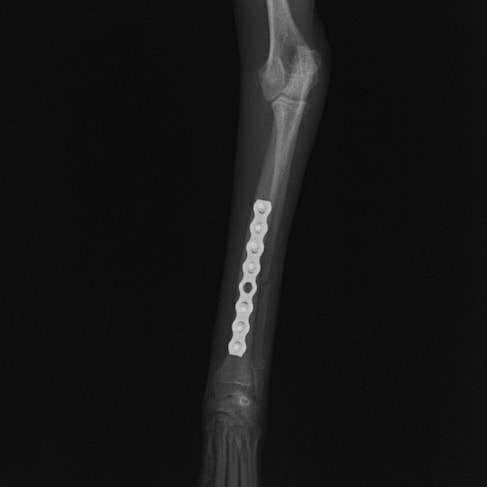

ペルシャ猫 11ヶ月齢 雄

他院にて左大腿骨遠位の成長板骨折(salter-harrisⅠ型)が認められており、治療相談を目的として来院。当院にて、キルシュナーワイヤーを用いたピンニングにより骨折部位の整復を行いました。術後の経過は良好で、現在も経過観察中です。

術後レントゲン

Arthrex社のターゲティングデバイスを用いてピンニングの位置を調整することで、確実な固定を行っています。当院ではこの手術器具以外にも、人の手術にも使用される様々な器具を導入し、手術精度を高め、また医療メーカーと新しい器具の開発、試作にも取り組んでおります。